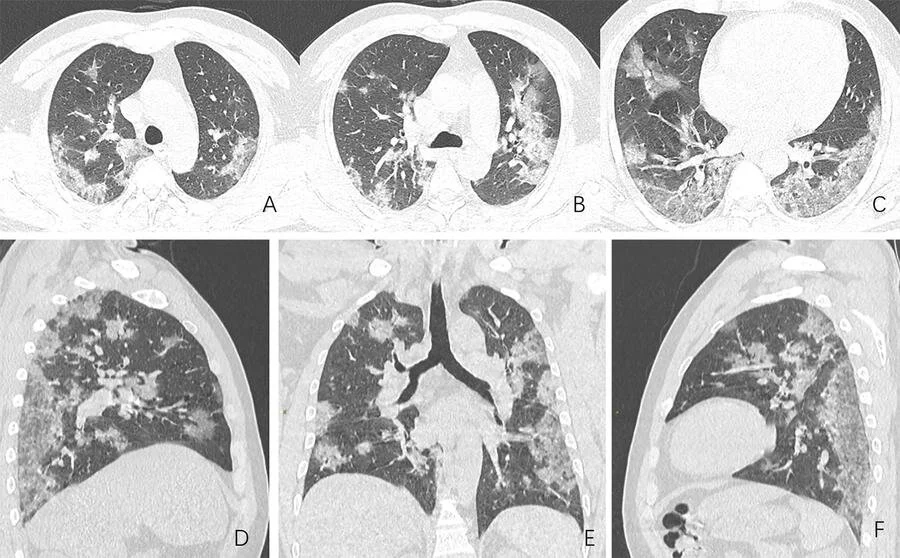

What COVID-19 Looks Like in the Lungs

COVID-19 is an infectious illness caused by a new coronavirus that can infect a person’s respiratory tract by latching onto receptors in healthy cells, especially in the lungs.